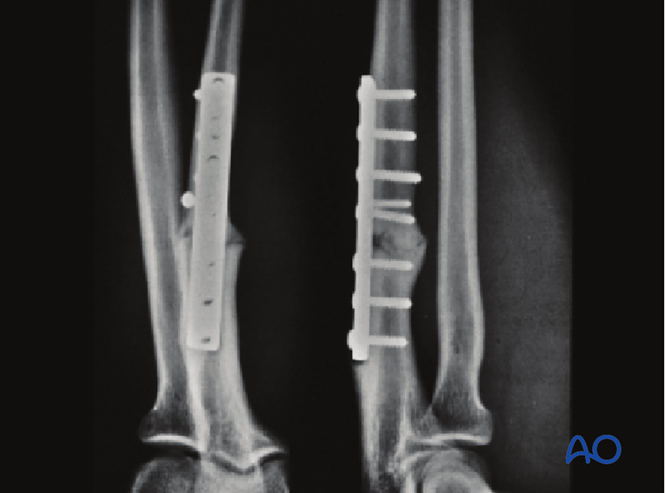

由于该骨折为粉碎性且极不稳定,术者决定先应用微型钢板以提供初始稳定性。

已植入微型钢板。其提供的稳定性足以支撑中和钢板的植入。

小钢板已复位骨折近端,骨折钳仍在原位。

此图显示复位钳和固定器已复位两处骨折。注意掌侧和背侧的软组织已小心地保留在骨折块上,以确保血供。

使用很长的锁定加压钢板(LCP)为这一复杂的尺骨中段骨折提供足够的固定。